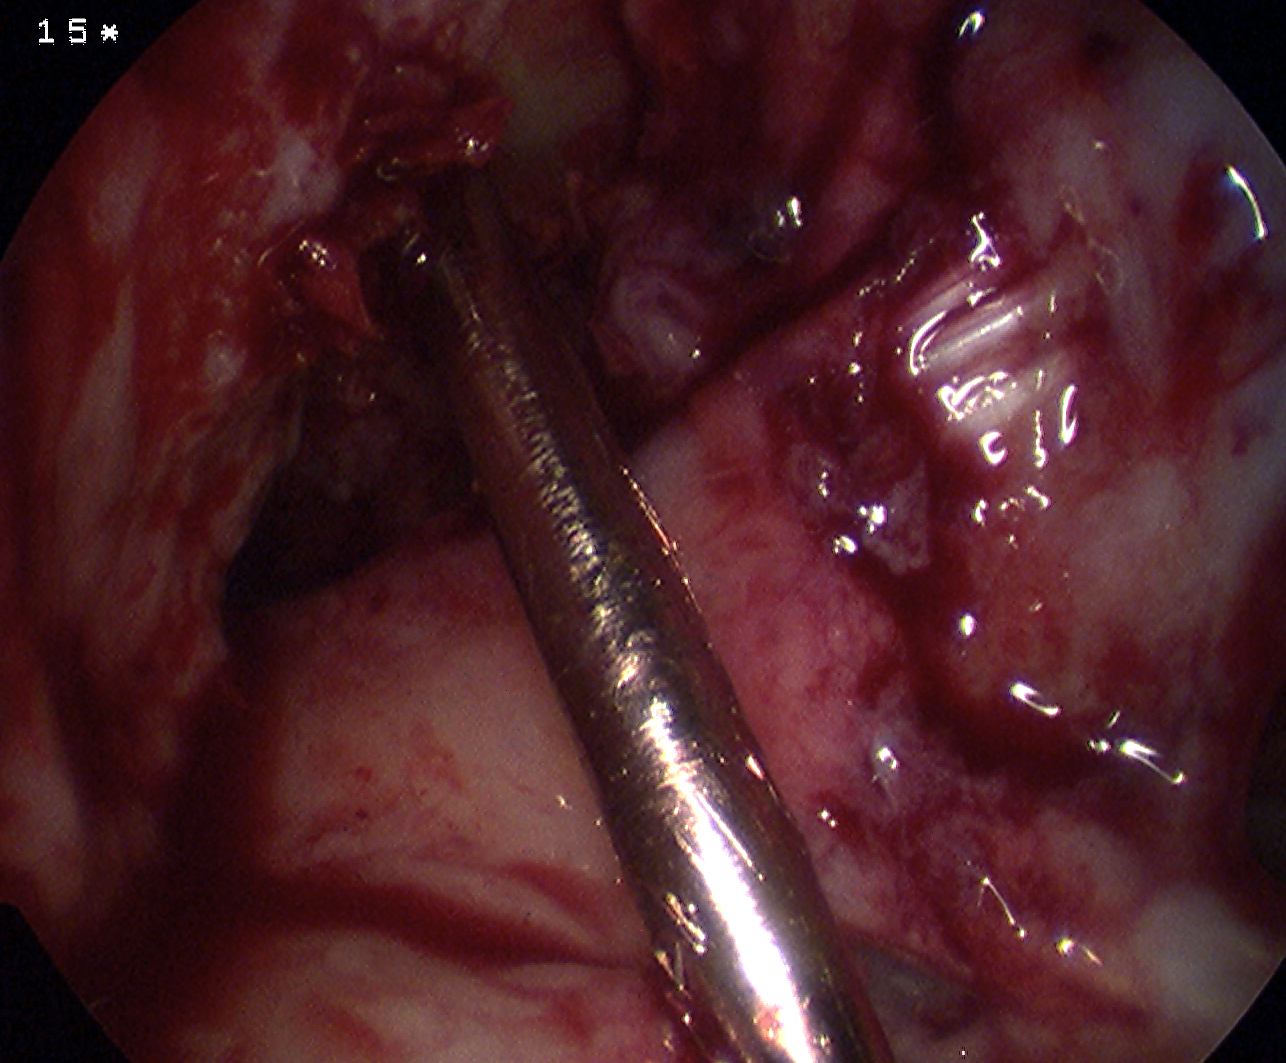

Prepare LFC

- notchplasty often required

- graft is significantly larger than HS